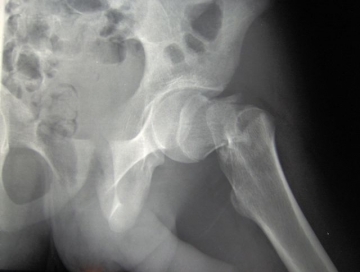

Najczęstszymi powodami wymiany stawu/stawów biodrowych są: bardzo poważne uszkodzenia kości budujących staw (np. bardzo częste złamanie szyjki kości udowej czy złamanie okolicy krętarza), zmiany zwyrodnieniowe stawów biodrowych i reumatoidalne Czytaj dalej